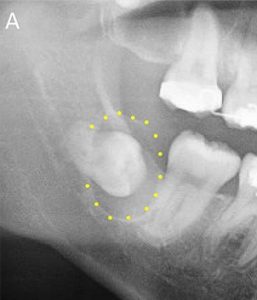

3.腫瘍や嚢胞の原因になっている

親知らずが原因で含歯性嚢胞(がんしせいのうほう)などの嚢胞や腫瘍ができる可能性があります。